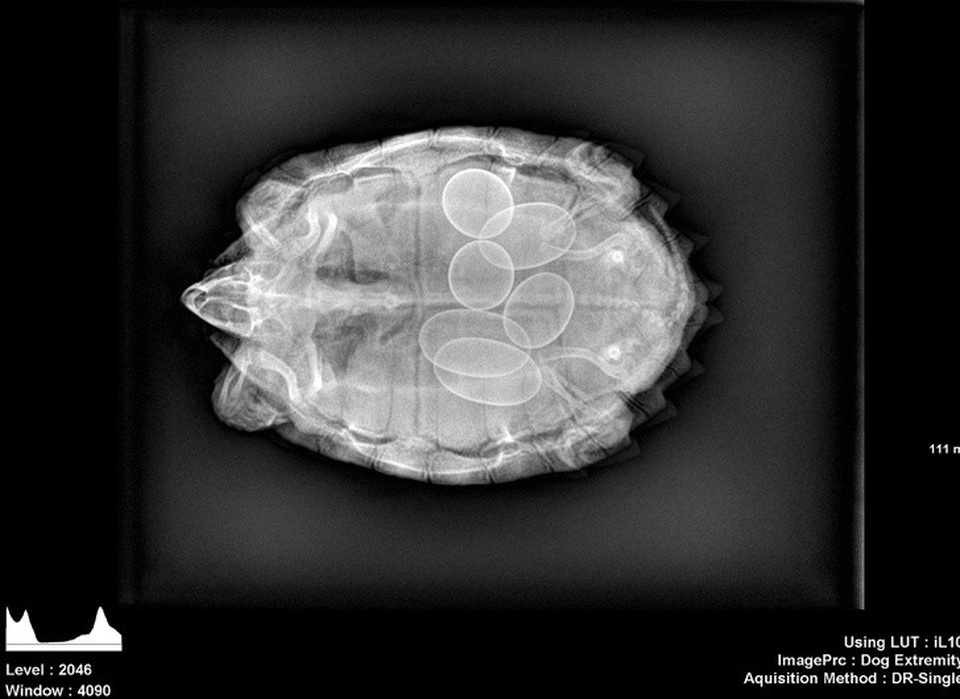

(Dân trí) - Hình ảnh chụp X-quang của những chủ thể đặc biệt như: một chú mèo đang mang thai, bộ phận cơ thể bị dị tật bẩm sinh hay thậm chí là bụng của cô bé nuốt nhầm chiếc bấm móng, được tổng hợp dưới đây, sẽ giúp bạn như bước vào một thế giới mà mình chưa từng biết!